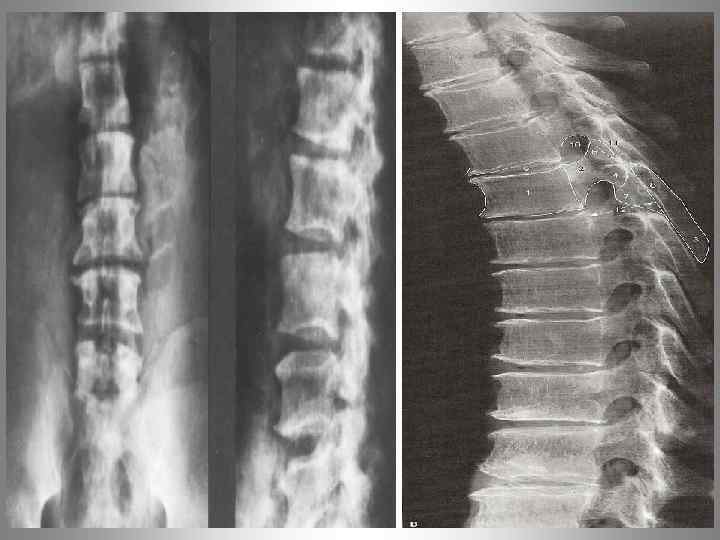

Метастаз. Патологический перелом тела Th 10 позвонка.